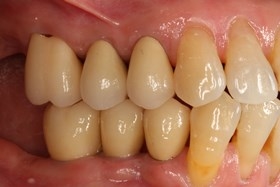

因植牙恢復正常咬合

口內照片